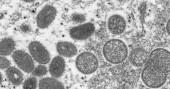

Monkeypox virus

The illness was first identified by scientists in 1958 when there were two outbreaks of a “pox-like” disease in research monkeys — thus the name monkeypox. The first known human infection was in 1970, in a 9-year-old boy in a remote part of Congo.

Monkeypox belongs to the same virus family as smallpox but causes milder symptoms.